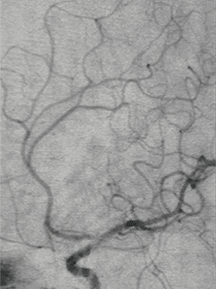

术后造影显示动脉瘤致密栓塞,不再显影;其它各分支血管通畅。

术后造影模拟血管重建显示支架头端完全覆盖动脉瘤瘤颈,并且与一期释放的支架远端形成“Kissing”。

支架:LEO+Baby支架2.5*12mm

弹簧圈:2*4-2D、1.5*2-2D